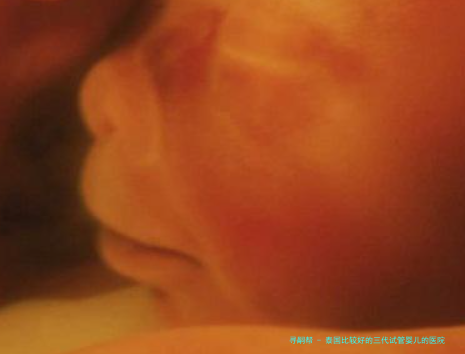

泰国比较好的三代试管婴儿医院:较安全、较、较专业的三代试管婴儿服务

泰国相比好的三代试管婴儿医院:能够综合的三代试管婴儿服务